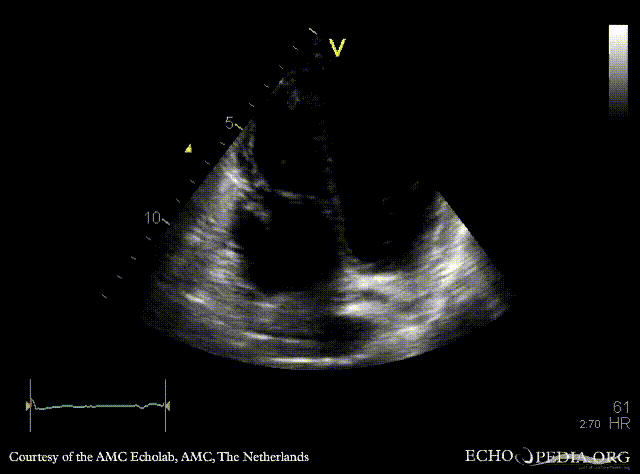

Case 48